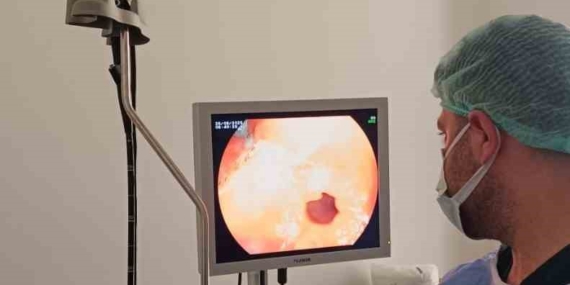

Çermik Devlet Hastanesi’nde Endoskopi ve Kolonoskopi Ünitesi Hizmete Girdi

Çermik Devlet Hastanesi’nde Endoskopi ve Kolonoskopi Ünitesi hizmete girdi. Güvenilir tetkikler ve konforlu süreçler için randevu alın.